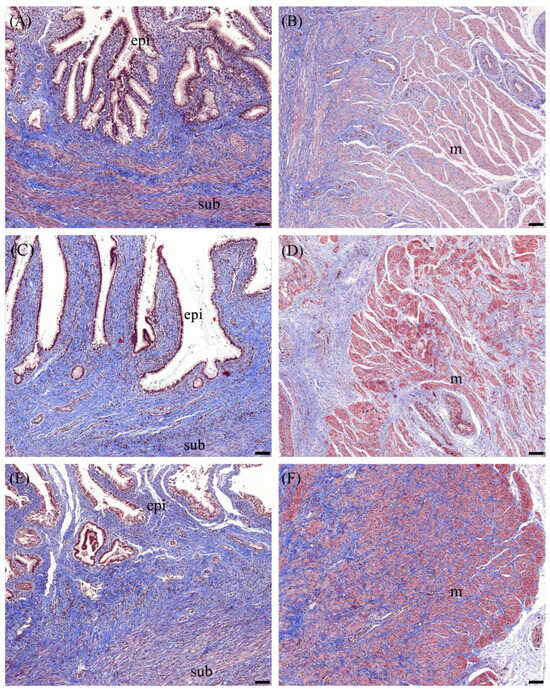

3.2. Masson Trichrome Staining

3.3. Alcian Blue Staining

| Masson trichrome (1) Subepithelial layer | ||||||||||

| Collagen | 38.94 | ± | 1.98 | 36.52 | ± | 2.20 | 36.12 | ± | 1.87 | |

| Cervical muscle | ||||||||||

| Collagen | 15.28 | ± | 1.12 a | 13.14 | ± | 1.16 a | 22.44 | ± | 1.05 b | |

| Alcian blue stain (2) | ||||||||||

| Epithelial layer | 14.52 | ± | 0.57 | 16.93 | ± | 0.58 | 15.43 | ± | 1.11 | |